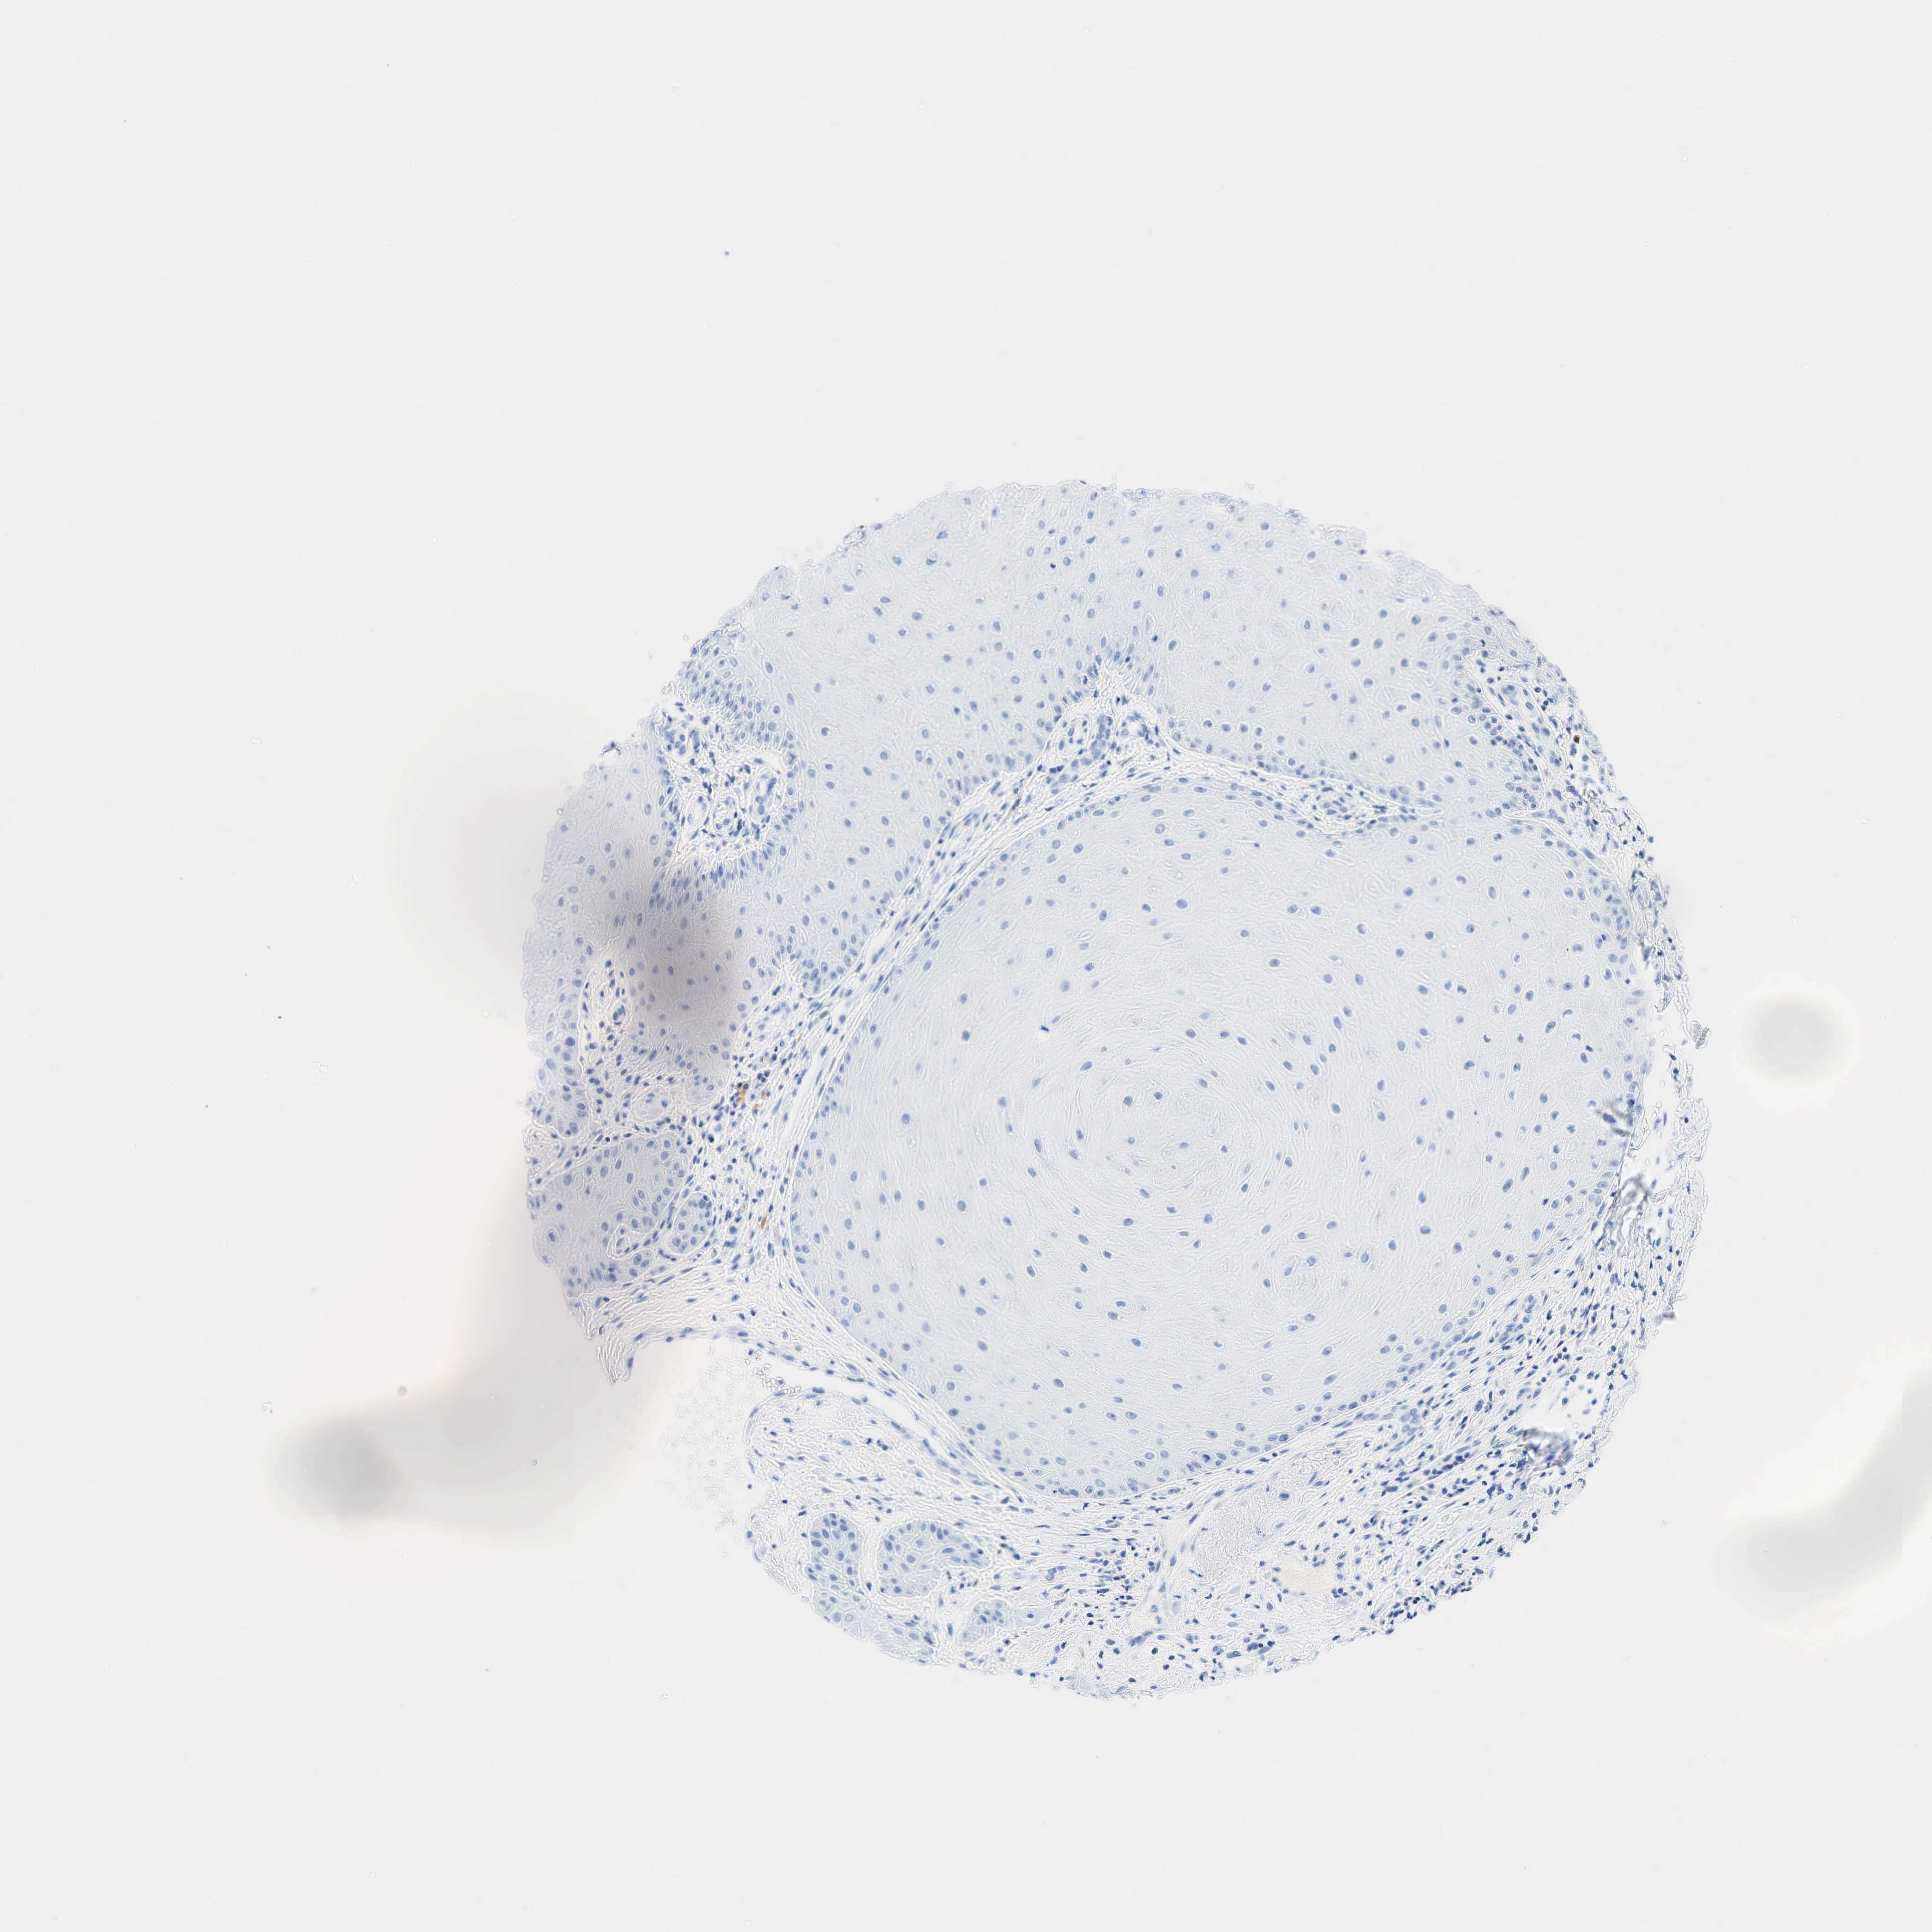

SKIN CANCER - Protein expressioni

A mouse-over function shows sample information and annotation data. Click on an image to view it in a full screen mode. Samples can be filtered based on level of antibody staining by selecting one or several of the following categories: high, medium, low and not detected. The assay and annotation is described here.

Antibody stainingi

Antibody staining in the annotated cell types in the current human tissue is reported as not detected, low, medium, or high, based on conventional immunohistochemistry profiling in selected tissues. This score is based on the combination of the staining intensity and fraction of stained cells.

Each image is clickable and will lead to virtual microscopy that enables deeper exploration of all samples and also displays staining intensity scores, fraction scores and subcellular localization as well as patient and tissue information for each sample.

Antibody HPA019141

Antibody CAB000047

Squamous cell carcinoma in situ, NOS